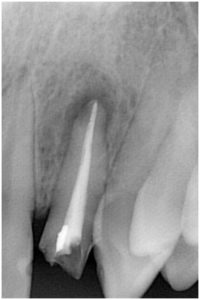

2枚目が根の治療を終えて薬を入れた時の写真です。根の先まできっちりと薬が入っているのが確認できます。